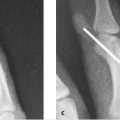

Pins, or Kirschner wires, are a versatile tool for fixation of metacarpal fractures. Closed approaches allowed by pinning can offer not only greater ease and lower morbidity than open approaches, but also achieve more reliable fixation in certain fracture patterns. Pinning options for common fracture patterns are reviewed, together with indications for pinning versus alternate approaches. Useful techniques for reduction and pinning are detailed and illustrated.

Metacarpal fractures represent one-fifth of all upper extremity fractures (264,000 every year) presenting to emergency departments in the United States. 1 Most can be treated nonoperatively. For most operative metacarpal fractures, percutaneous pinning after closed or open reduction is a powerful and versatile technique that can be applied in a myriad of combinations to address individual fracture patterns.

Closed reduction and pinning has specific advantages over open approaches. It may decrease postoperative swelling and stiffness that follows open reduction. In many scenarios, plate and screw fixation may require extensive dissection and disruption of soft tissue attachments, even after difficult reduction requiring open treatment. In these cases, it is usually preferable to employ wire fixation. A comminuted intra-articular fracture may be managed with a closed pinning approach to take advantage of ligamentotaxis. Similarly, extra-articular commin-uted fractures may reduce easier when the soft tissue envelope is preserved. Kirschner wires (K-wires) may also be preferable in comminuted fractures, given the potential lower risk of fragment devitalization due to periosteal stripping.